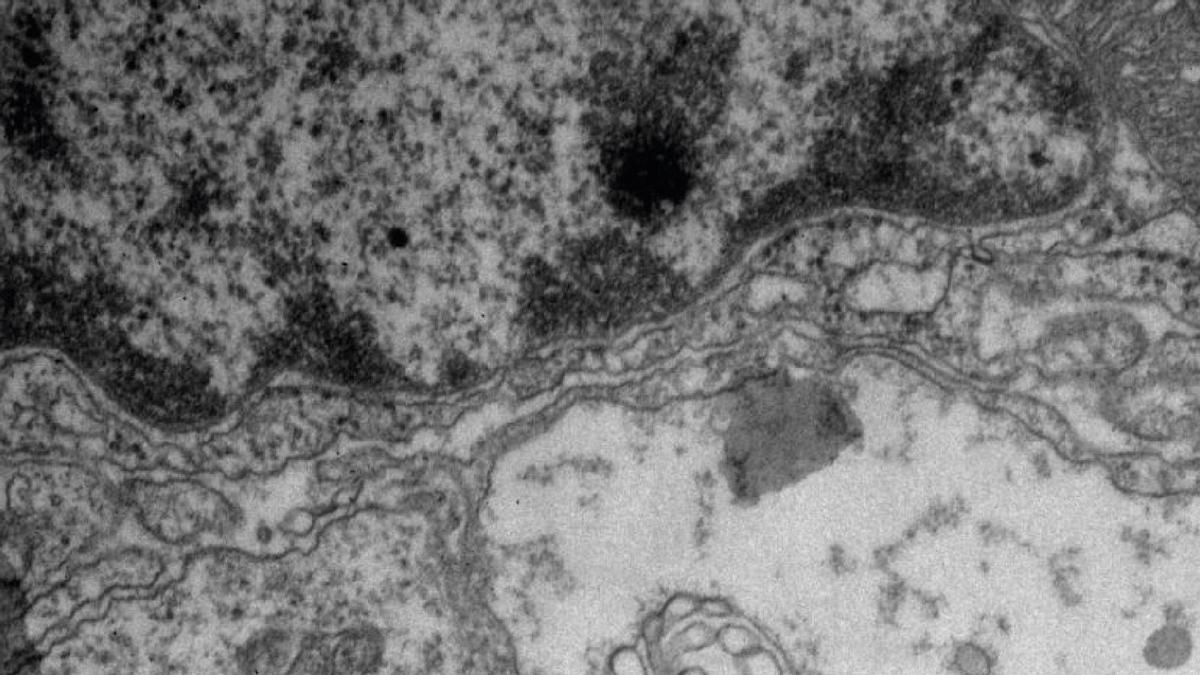

Imagen de una de las células. / EL PERIÓDICO

La revista Sientific Reports recoge un estudio pionero realizado por Investigadores del Instituto de Investigación Sanitaria Aragón y de la Universidad de Zaragoza centrado en tumores cerebrales de bajo grado. El equipo, dirigido por la Dra. Concha Junquera, Catedrática de Biología de la Universidad de Zaragoza e investigadora del IIS Aragón, empleando microscopia electrónica ha identificado que los gliomas de bajo grado emplean unas vesículas que se conocen como esferosomas. “Estos esferosomas se producen en las células tumorales y se liberan al medio extracelular para trasportar información a las células vecinas o a otras células lejanas a través de los vasos”, apunta la doctora.

Las vesículas extracelulares más estudiadas son los exosomas. Sin embargo, este equipo ha encontrado que otras vesículas, los esferosomas, son más habituales en estos tumores cerebrales. El equipo ha descrito con mucho detalle el origen de estos esferosomas y cómo se producen encontrando que es muy distinto a los exosomas. “Los esferosomas tienen diferente origen y biogénesis que los exosomas hallados en otros tumores y presumiblemente transportan diferentes moléculas,es decir, diferente contenido o información, lo que sugiere que desempeñan funciones distintas en la progresión de estos tumores cerebrales”-explica Marta Baselga, primera firmante del trabajo.